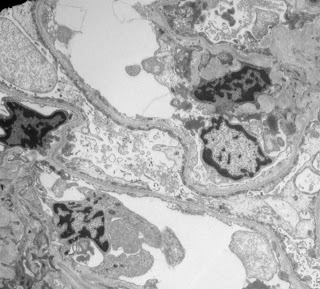

Low power view of the renal cortex showed mild chronic parenchymal changes that would not be unusual for someone of her age – 2/20 glomeruli were sclerosed and there was focal tubular atrophy and interstitial fibrosis affecting less than 5 percent of the parenchyma

Her glomeruli looked normal with no evidence of inflammation or mesangial expansion.